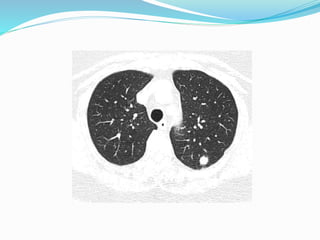

Nodules

 May be solitary or multiple.

 Rounded nodules of variable sizes ranging from few

millimeters to few centimeters with well-defined margin.

75 % - multiple pulmonary nodules.

Nodules  May besolitary or multiple.  Rounded nodules of variable sizes ranging from few millimeters to few centimeters with well-defined margin. 75 % - multiple pulmonary nodules.  Commonest tumours producing solitary pulm. nodules are carcinomas of – • Colon • Kidney • Breast • Testicular tumours • Bone sarcomas • Malignant melanoma.